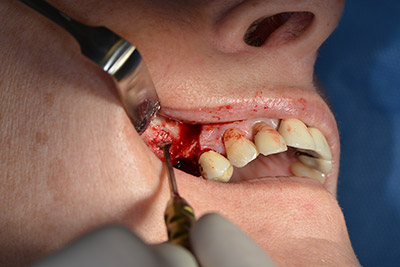

Dunque, l'impianto viene posizionato e l'osso ricostruito. In questo caso, considerate le dimensioni della regione di accrescimento, i microframmenti dell'osso autologo (raccolti con un'apposita cannula di aspirazione in seguito alla perforazione dell'impianto 16 e della fenestrazione 14) vengono combinati con dei materiali di riempimento dell'osso.

Una membrana riassorbibile viene usata come barriera in direzione buccale per contenere l'accrescimento. Infine, vengono applicate suture resistenti alla saliva (da fig. 15 a 19).

Accrescimento con osso autologo

Immagine 15

Immagine 16

Impianto

Immagine 17

Implantologia

Immagine 18

sutura della ferita a prova di saliva

Immagine 19